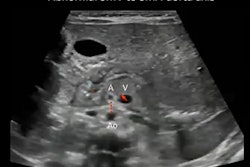

Lung ultrasound was performed in the supine, prone, and decubitus position using a portable ultrasound system (Mindray M9, Mindray Medical) and a linear-array probe with a frequency of 4-12 MHz. Lung aeration loss was estimated using a validated lung ultrasound score. The chest wall was divided into 12 regions (six regions per hemithorax).

The anterior and posterior axillary lines designated practical landmarks that demarcated the anterior, lateral, and posterior areas of both lungs, and delineated the nipple line defining the upper and lower halves. A semiquantitative lung ultrasound score identified four progressive stages of lung aeration loss with an assigned score from 0 to 3. A score of 0 indicated normal aeration, while a score of 3 indicated a complete loss of aeration.

For the COVID‐19 group, the researchers examined a total of 132 regions of the lung, 62.8% of which showed abnormalities detected by lung ultrasound. Compared with controls, COVID‐19 neonates showed sparse or confluent B‐lines (83 regions), disappearing A‐lines (83 regions), abnormal pleural lines (29 regions), and subpleural consolidations (2 regions).

The lung ultrasound score was significantly higher in the COVID‐19 group with 49 regions (37%) presenting as normal, 73 regions (55%) scoring 1, and 10 regions (8%) scoring 2. All lesions were bilateral and involved multiple regions with the majority located in the bilateral inferior and posterior regions.